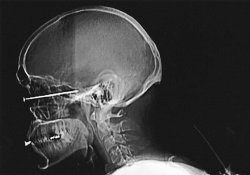

Невероятный случай удивительного везения произошел в Китае. Житель столицы страны, который решил отремонтировать квартиру собственными руками, подгоняя доски до нужной длины с помощью специального станка, не заметил в одной из них большого гвоздя…

Необычного пациента пришлось оперировать врачам одной из немецких клиник: только после тщательного обследования медики обнаружили в одной из придаточных пазух его носа карандаш. Больной вспомнил одно происшествие, случившееся еще более 15 лет назад.